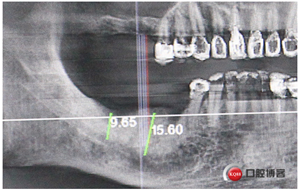

中年男性,右上右下后牙缺失,上頜竇底骨高度3mm,身體健康無(wú)不良習(xí)慣。

計(jì)劃:1.右上6,7外提升同期植入植體

2.右下5,6,7種植